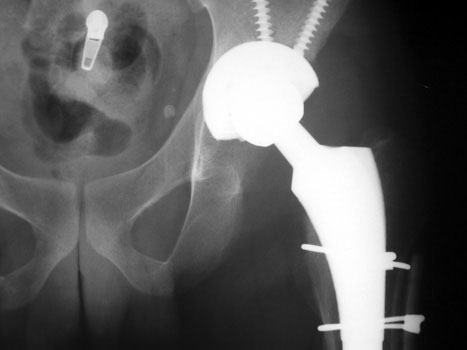

INFECTION

Resection of hardware, flail hip

Resection of hardware, cement spacer placement

Cement spacers are antibiotic impregnated, allowing for local dispersal of antibiotics.

• Maintain leg length

• Minimize dead space

• Preserve soft tissue planes

• Facilitate ease of revision arthroplasty

Cement spacers are fabricated in the surgical suite using methylmethacralate cement impregnated with antibiotics sensitive to cultured organisms. A Rush rod is cut and bent to 120 degrees to mimic the femoral neck-shaft angle. Antibiotic impregnated cement is placed into a blue bulb syringe which simulates the femoral head contour and allowed to dry. The plastic is then removed. A second batch of cement is prepared and formed around the femoral shaft portion of the Rush rod.